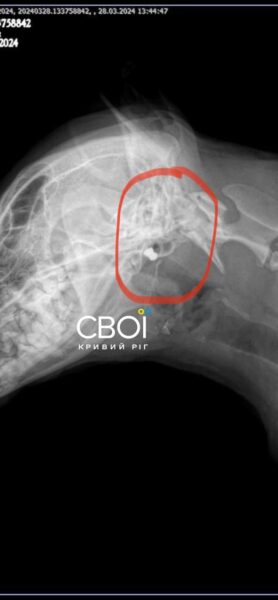

Ветеринар назначил лечение для Бати. Одна из пуль застряла в голове животного, другая — возле желудка. Достать их, чтобы не навредить собаке, невозможно.